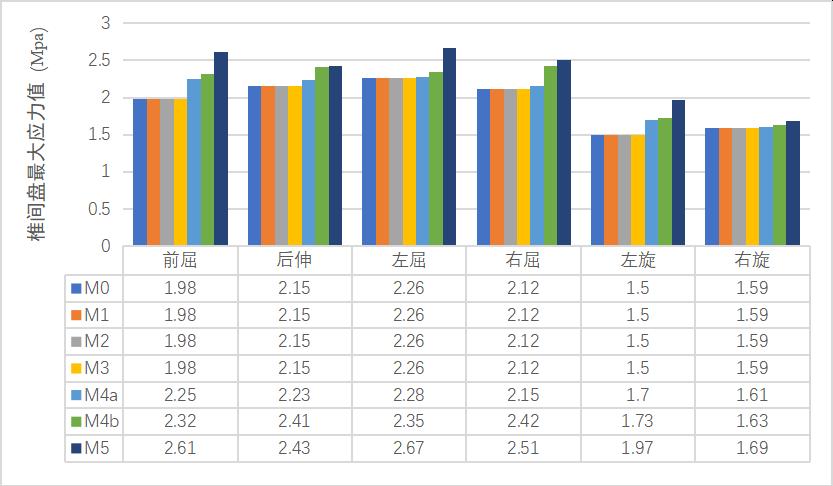

2����、0-2级成型(M1-M3)因没有进行骨质的切除��,所以对腰椎稳定性没有明显的影响����。3-4级成型时(M4a���、M4b�����、M5)����,L3-4节段在左旋及右旋时的活动度变化最大���,其中左旋由24.15%增加到30.34%����,右旋由27.81%增加到91.42%���,在前屈及左旋时的椎间盘应力值变化最明显���,其中前屈由13.64%增加到31.82%��,左旋由13.33%增加到31.33%��。L4-5节段在后伸时的活动度变化最大��,由46.49%增加到66.96%���,在前屈时的椎间盘最大应力值变化最大����,由19.12%增加到37.50%���,见表3-8��。

(2)椎间盘最大应力值变化

表格 6 成型后L3-4椎间盘最大应力值变化

表格 7 成型后L4-5椎间盘最大应力值变化

表格 8 L3-4���、L4-5节段3-4级成型后椎间盘最大应力值与正常模型比较